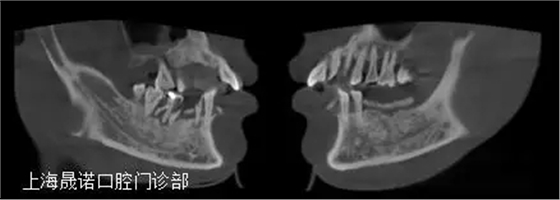

男46歲 患者主訴: 下頜牙缺損伴疼痛,無法滿足日常飲食需求,要求修復(fù)。 診斷: 牙列缺損,中晚期牙周炎。 治療方案: (1)確定終修復(fù):種植體支持的全牙弓一體式 CAD/CAM全鈦烤塑復(fù)合橋。 (2)種植外科前面弓轉(zhuǎn)移,確定咬合關(guān)系。 (3)根據(jù)R2GATE制作標(biāo)準(zhǔn)拍攝CBCT。 (4)R2GATE種植方案確定及生成。 (5) 種植外科:結(jié)合臨床條件及R2GATE植入EZPlus,鎖定八角基臺。 (6)即刻負(fù)重:被動性印模,當(dāng)日完成種植體支持的螺絲固位臨時橋修復(fù)體。 (7)終修復(fù):依據(jù)患者臨時橋修復(fù)體的佩戴情況,評估及完成終修復(fù)。終修復(fù)為全牙弓一體式CAD/CAM全鈦烤塑復(fù)合橋。 (8)隨訪和專業(yè)口腔衛(wèi)生維護(hù):第一次3個月;第二次半年~一年。放射對照性檢查為每年一次。 術(shù)前口內(nèi)檢查 術(shù)前影像檢查分析 種植位點設(shè)計 種植位點評估 R2GATE導(dǎo)航系統(tǒng)設(shè)計種植體分別為 右下4:EZplus 4*11.5mm; 右下6:EZPlus 4.5*10mm; 左下5:EZPlus 4*10mm; 左下6:EZPlus 4.5*10mm; 左下7:EZPlus 4.5*7mm. R2種植導(dǎo)板 收到R2GATE導(dǎo)板及手術(shù)報表,導(dǎo)板外科工具盒。 治療步驟 第二周9:30-11:30:摘除R2GATE,33、43即拔即種。拔除34、44、45、46;口內(nèi)就位R2GATE,44、46、35、36、37不翻瓣導(dǎo)航下完成全程備洞。 35(EZPlus 4.0*10mm) 36(EZPlus 4.5*10mm) 37(EZPlus 4*8.5mm) 33、43(EZPlus 4.0*13mm) 44(EZPlus 4.0*11.5mm) 46(EZPlus 4.5*10mm) 植入扭力都大于50Ncm,分別35N鎖定八角基臺,并用手?jǐn)Q緊八角愈合帽,將骨引導(dǎo)材料(Bio-Oss,Geistlich)植入骨缺損區(qū)。

分別設(shè)計位點于右下3,4,6,左下3,5,6,7。綜合考慮后,為獲得更優(yōu)的導(dǎo)板固位,決定保留雙側(cè)尖牙支持導(dǎo)板,導(dǎo)航下植入右下4,6;左下5,6,7;摘除導(dǎo)板后,雙側(cè)尖牙進(jìn)行即拔即種。